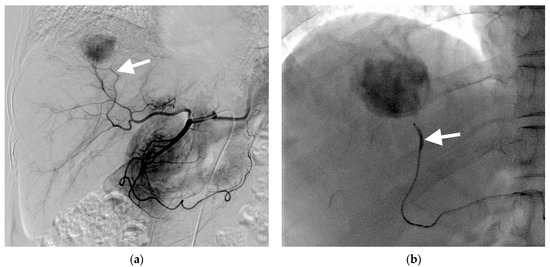

3.1. B-TACE Procedure and Complications